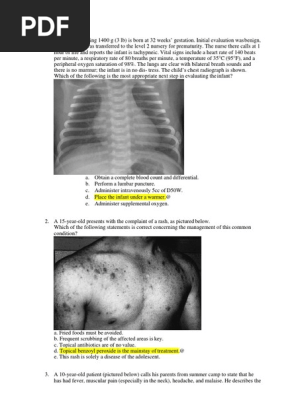

Pneumothorax chat suite chute

Pneumothorax chat suite chute-Si plusieurs ponctions sont nécessaires pendant 24 heures, un drain thoracique peut être posé Une prise en charge chirurgicale est parfois nécessaire Lors de chute de plusieurs étages, un pneumothorax peut être présent mais entraine une dégradation sévère de l'animal dans les 24 heures suivant le choc Bibliographie1701 · Pneumothorax A pneumothorax describes the condition in which air has become trapped next to a lung Most cases occur 'out of the blue' in healthy young men Some develop as a complication from a chest injury or a lung disease The common symptom is a sudden sharp chest pain followed by pains when you breathe in

· Pneumothorax traumatique Renseignements cliniques Bagarre dans un couple Chute dans les escaliers Nombreuses ecchymoses Douleurs thoraciques Se présente au Service d'Accueil et des Urgences pour soins et certificat médical Gril0115 · Tout traumatisme direct (choc en sport, chute d'un lieu élevé, accident de la route, etc) ou indirect (éternuement, toux, contraction violente des muscles intercostaux) peut entraîner une fracture d'une ou de plusieurs côtes Un enfoncement de la côte vers le poumon peut s'accompagner d'un pneumothorax (de l'air entre dans la plèvre) ouRadiographie d'un pneumothorax chez un chat tombé du 3 ème étage La chute du balcon estelle une urgence vétérinaire?

1606 · Avis radio chat suite chute du 2 ème étage Je voudrais des avis de vétérinaires sur la radio ci dessous de mon chat suite à une chute du 2ème étage Que fautilSelon les vétérinaires donc « le syndrome du chat parachutiste ou highrise syndrome (HRS) correspond aux lésions dues à une chute en partant du deuxième étage Outre l'état de choc le bilan des lésions se manifeste le plus souvent par la triade lésions pulmonaires (contusion pneumothorax) contusions de la tête et fracture appendiculaireQuelque soit la hauteur de la chute, l'âge de votre animal et les lésions extérieures, une chute du balcon ou d'une fenêtre est une urgence vétérinaire possiblement vitale La consultation s'impose